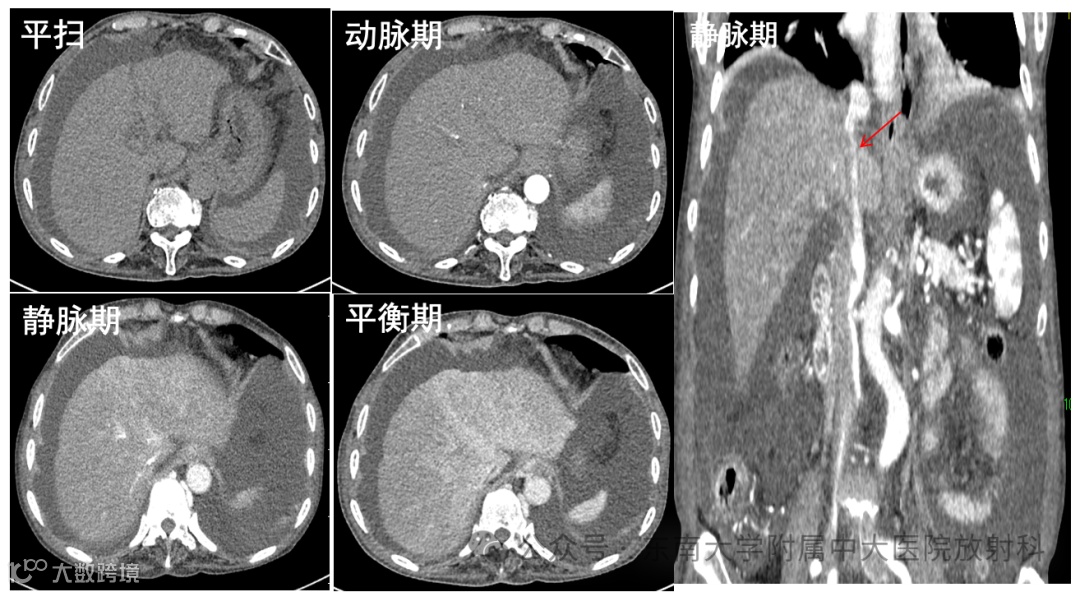

病例1

女性,76岁 -

主诉:腹胀伴双下肢水肿20天 -

现病史:患者服三七药酒半年余后,20天前出现腹胀伴双下肢水肿,伴纳差乏力,偶有右季肋区隐痛,程度尚可忍受,伴活动后气喘,无消瘦等不适。外院全腹CT增强:右侧升结肠CA?肝弥漫性脂肪浸润,肝内门静脉主干及分支栓塞,双侧胸腔、腹腔积液。肝功能:ALT 61.1U/L,AST 132.5U/L,凝血功能轻度异常。予保肝、利尿、补充白蛋白、抗凝、引流腹水等治疗,各项指标仍有进展,急诊拟“肝小静脉闭塞综合征”收治入院。 -

既往史:有“肝炎”病史,具体不详。 -

影像学表现